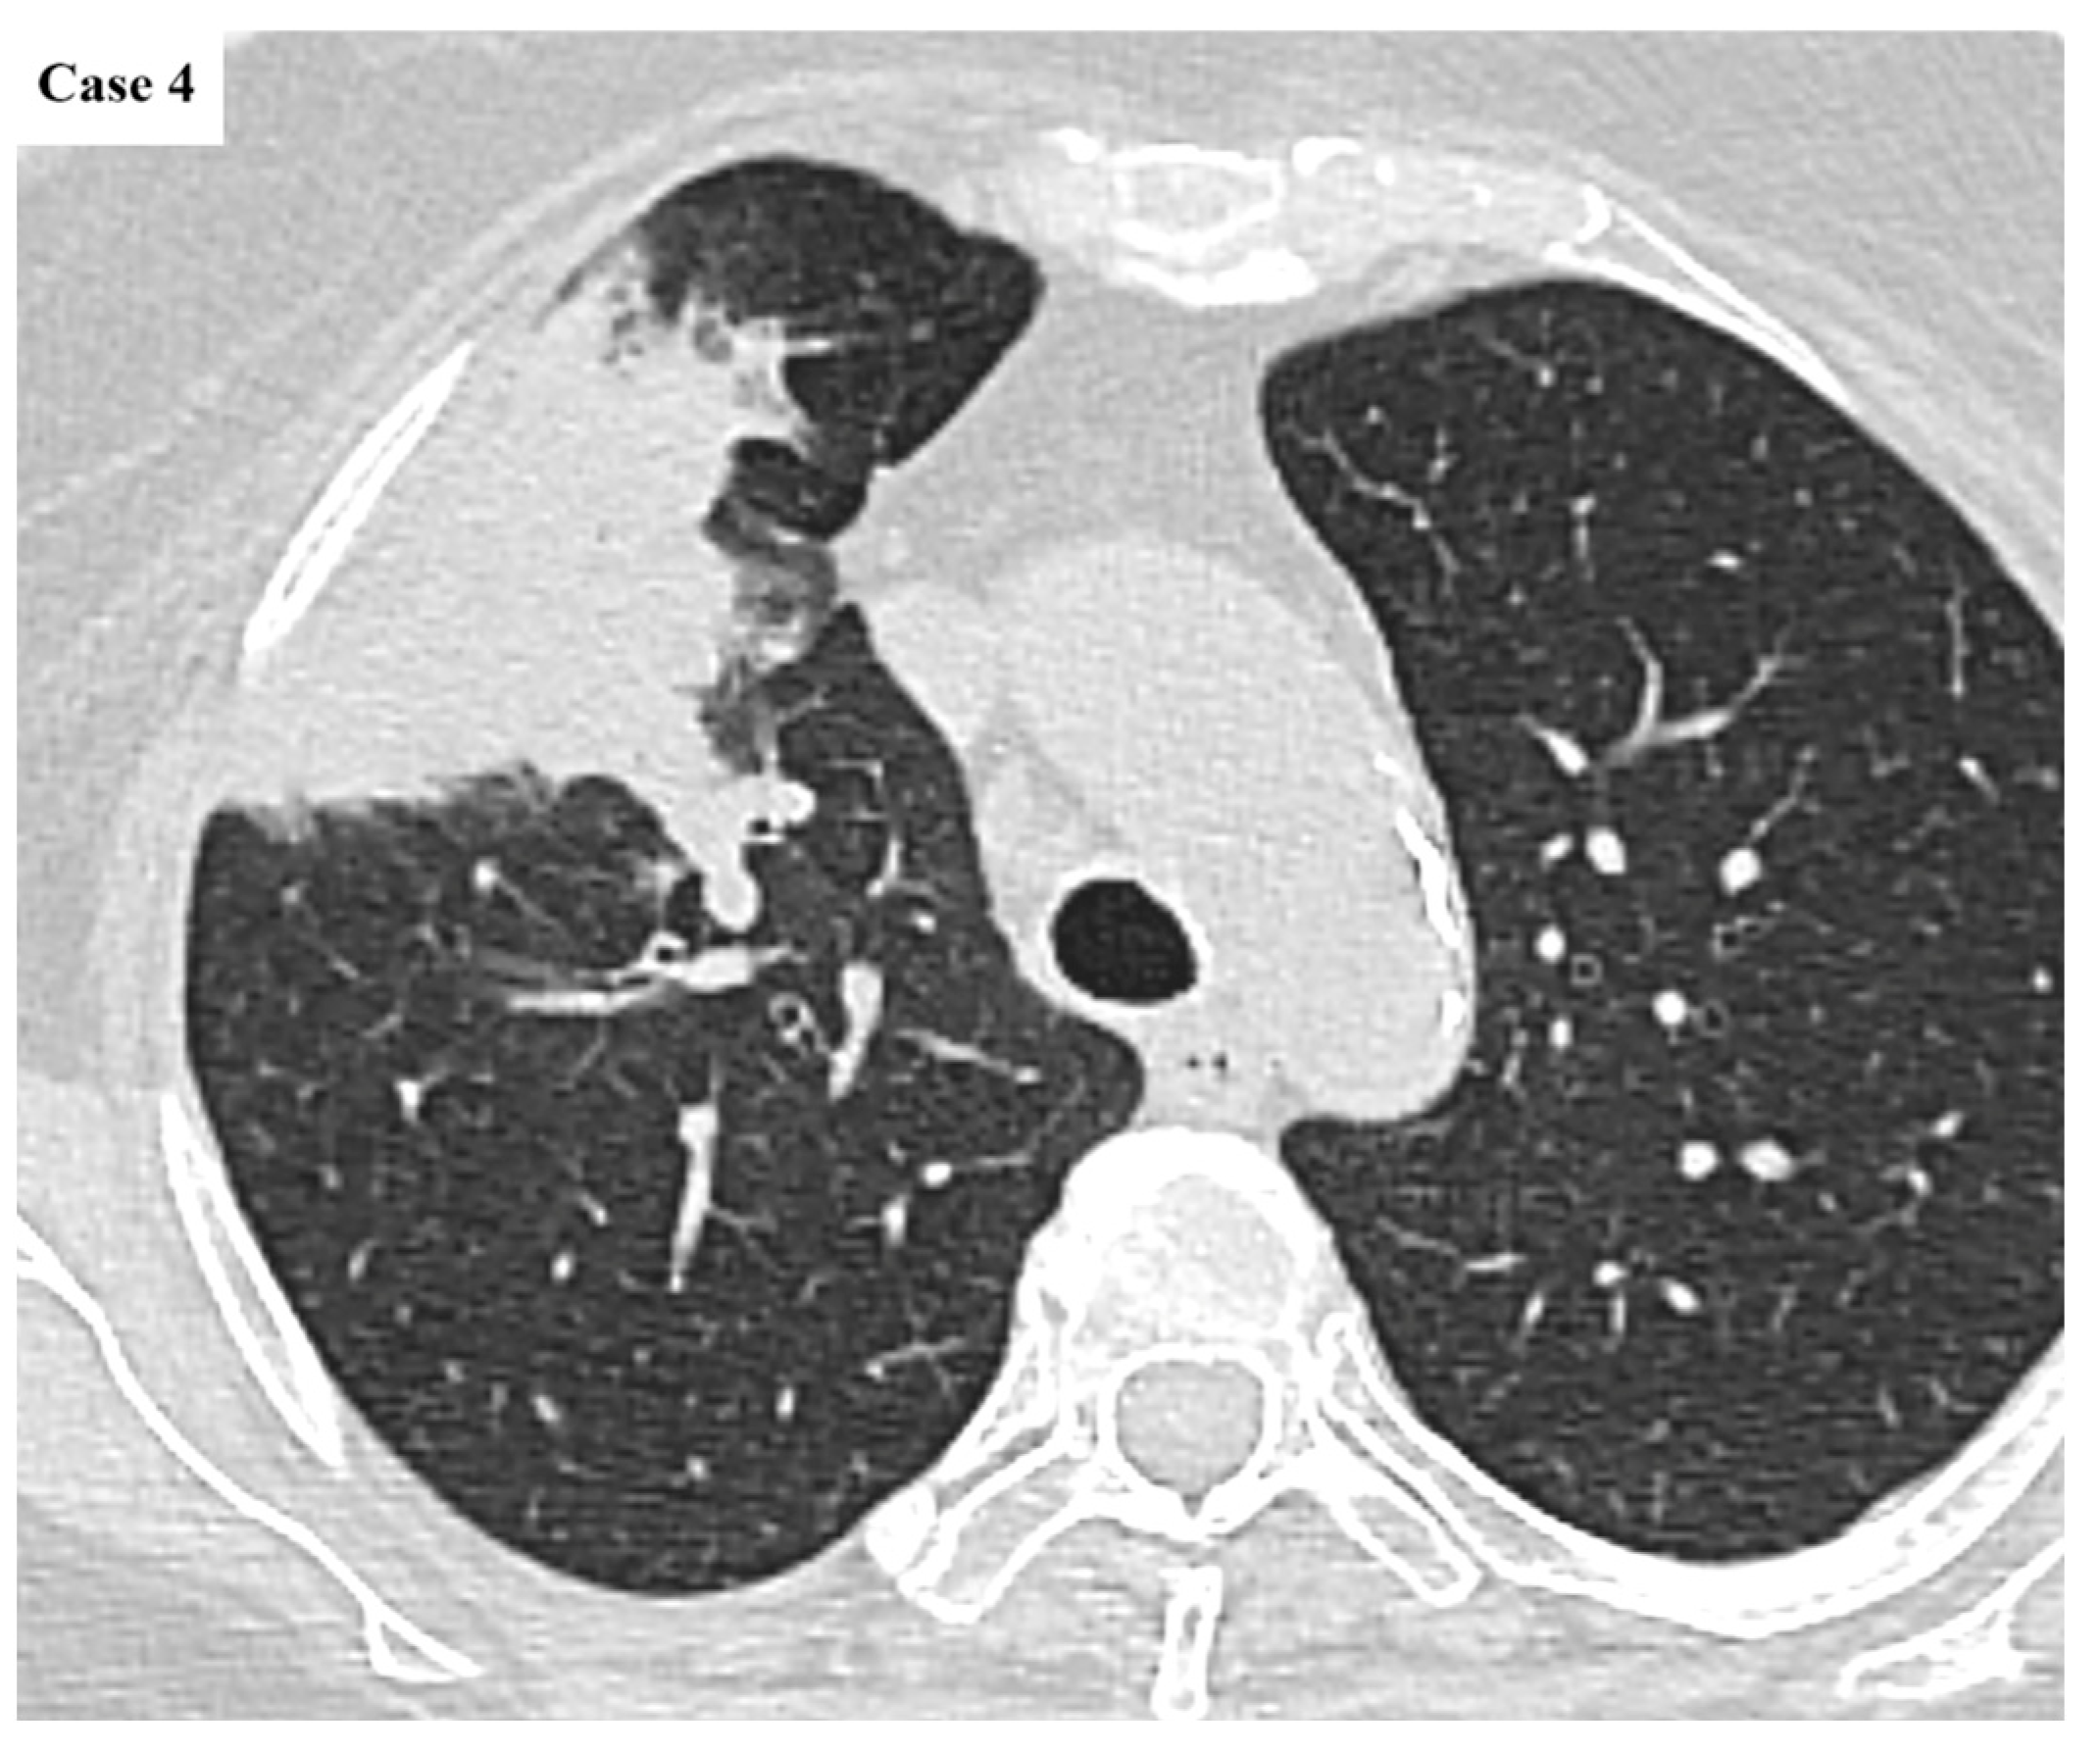

| Tumor size (cm) | Median 4.2 (IQR 2.6–5.9) |

| Imaging features | Spiculated margins: 88% Central necrosis: 38.4% Cavity: 10.4% Lymphangitic spread: 43.2% |